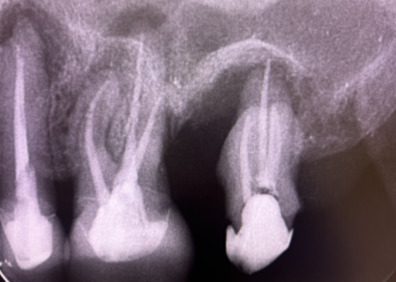

虫歯が進行すると、歯の神経(歯髄)にまで感染が広がります。この段階では、感染した神経を取り除き、根管(神経が通る管)を丁寧に清掃してから被せ物を施す治療が必要です。「根管内を徹底的に清掃する作業」は非常に難しく、慎重な処置が求められます。根管は複雑に分岐しており、清掃が不十分だと「痛み」や「腫れ」などの症状を引き起こし、最終的に「根尖病巣」と呼ばれる病気に繋がることもあります。下の画像の「黒い部分」は、神経が入っている根管であり、この部分をすべてしっかりと清掃しなければなりません。